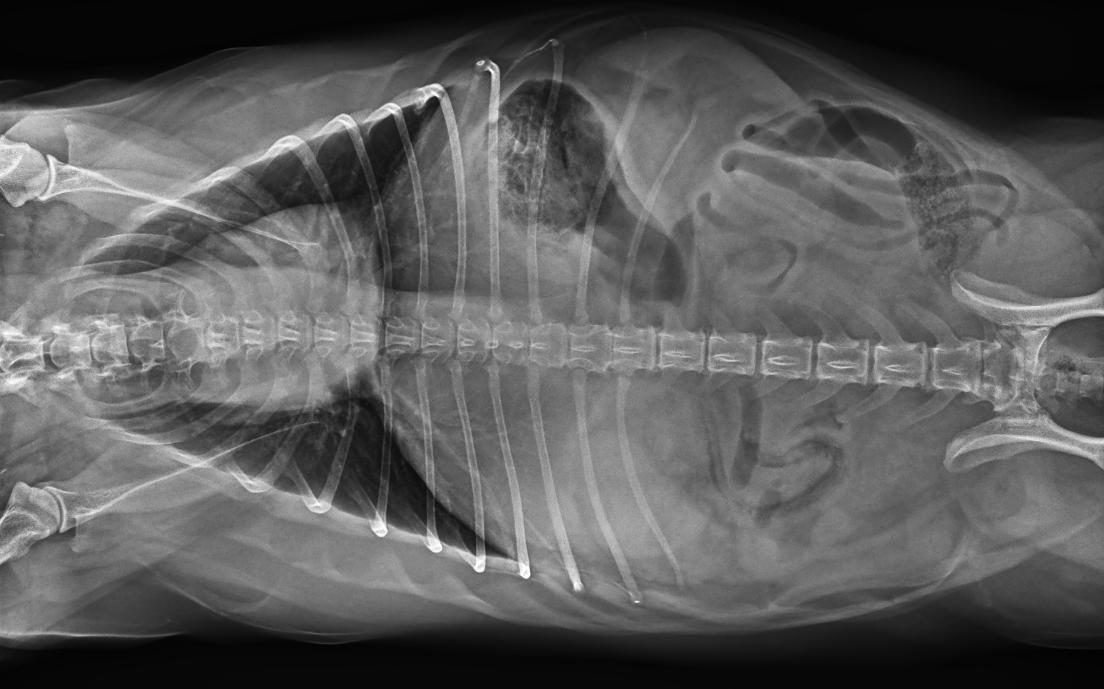

● 17*17大尺寸平板探測(cè)器,獲得高質(zhì)量圖像

● 優(yōu)異的空間分辨率及信噪比,提升圖像質(zhì)量

● 采用線噪聲消除技術(shù),使成像質(zhì)量提升40%

● 智能高效的圖像處理軟件,大幅提升圖像質(zhì)量